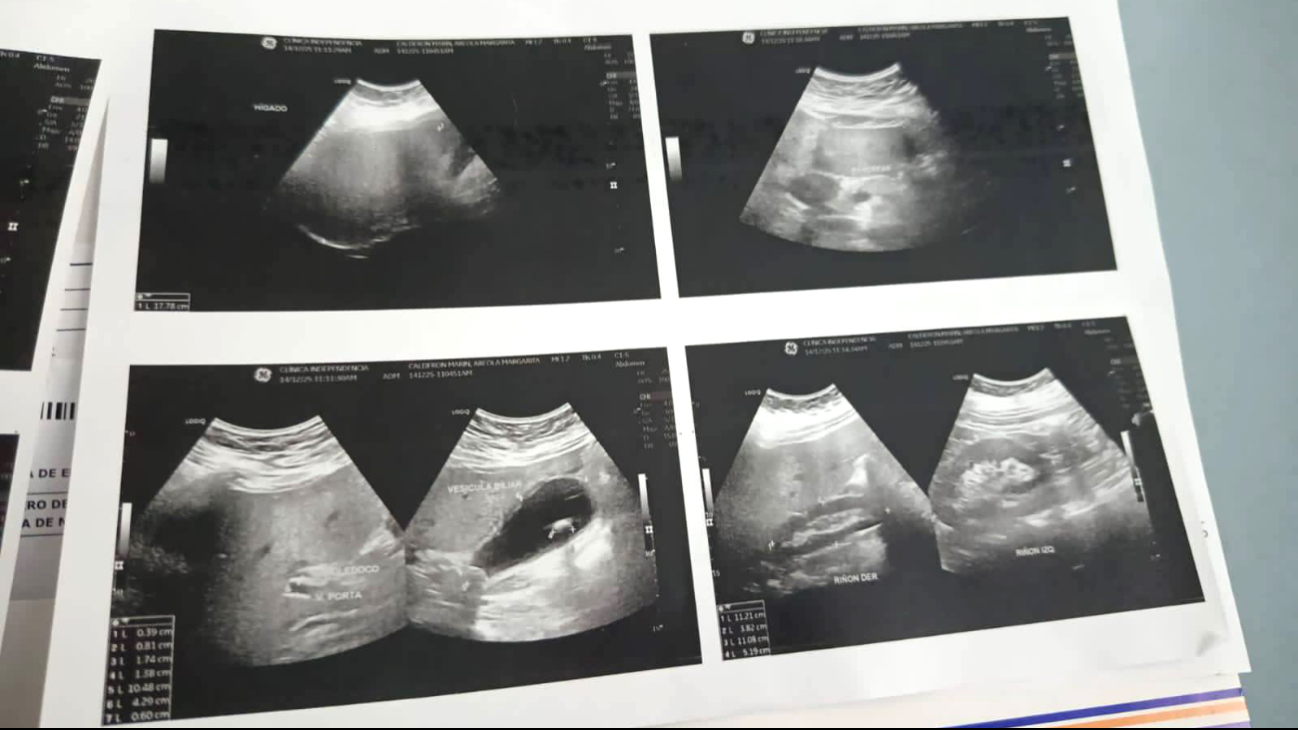

Debido a esta omisión, la paciente tuvo que ser trasladada a una clínica privada para someterse al estudio médico, cuyo costo fue cubierto por sus familiares. Los resultados revelaron la presencia de cálculos en la vesícula, uno de los cuales la obstruye, provocando una lesión que podría derivar en una infección grave si no se atiende oportunamente. No obstante, en el ISSSTE aún no se le han practicado los análisis necesarios para confirmar dicha complicación.

Paciente con cálculos en la vesícula enfrenta omisiones y falta de atención en el ISSSTE

Paciente con cálculos en la vesícula enfrenta omisiones y falta de atención en el ISSSTE / Anahí Chamlati